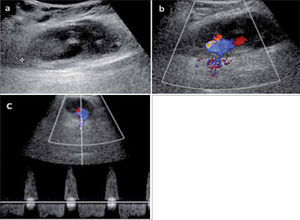

2Presencia de vascularización en una lesiónEs importante porque permite describir que una lesión es sólida cuando encontramos estructuras vasculares en su espesor o que una lesión “quística”, presenta flujo, como en los pseudoaneurismas (fig 9). También se determina la naturaleza de los vasos, si son de predominio arterial, venoso o si constituyen shunts.